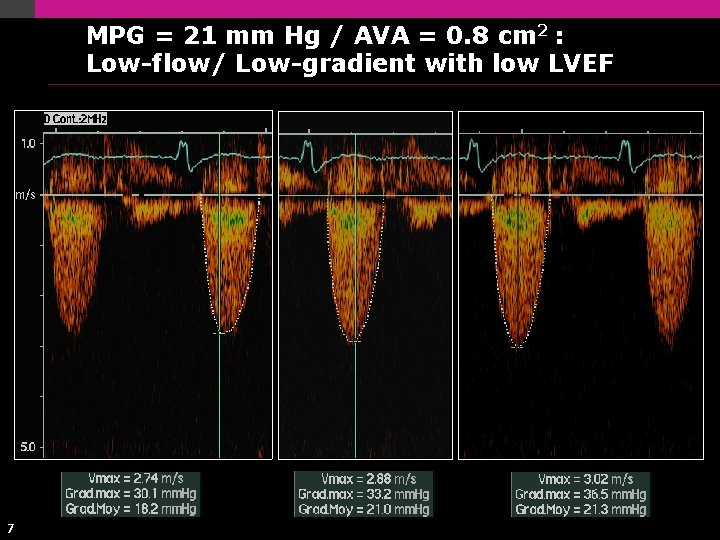

MPG = 21 mm Hg / AVA = 0. 8 cm 2 : Low-flow/ Low-gradient with low LVEF 7